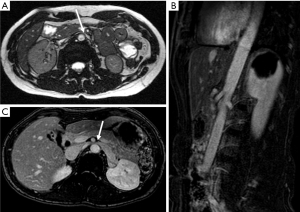

MRI is particularly beneficial in children and adolescents owing to the absence of radiation while retaining the ability to evaluate adjacent abnormal vascular structures, such as an enlarged gonadal vein (40). Vein diameter ratios and “beak sign” can be evaluated in similar fashion as CT (Figure 6). A comparison of various MRI sequences determined that True Fast Imaging with Steady-State Free Precession (T2-TRUFI) has particularly good image quality for evaluating the LRV (41). High signal intensity in the LRV on fast-spin-echo T2-weighted sequence due to venous hypertension and stagnation may be particularly useful for diagnosis and evaluating response to therapy (42).